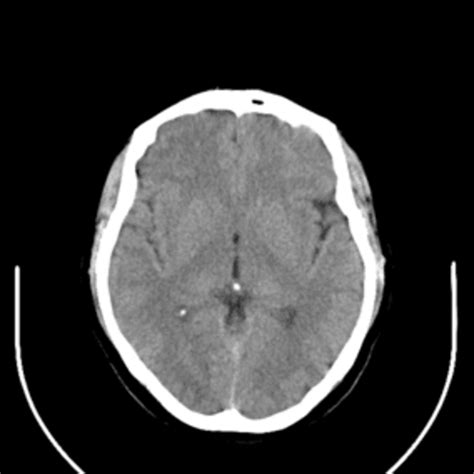

Brain stroke dataset kaggle. This research takes a new direction by applying machine learning techniques to predict the likelihood of cerebrovascular accidents, or simply strokes, from an extensive dataset that was meticulously We share a large dataset of clinical acute stroke MRIs, associated to demographic and clinical metadata, in alignment with the broad aim of the biomedical community to share FAIR data. We’re on a journey to advance and democratize artificial intelligence through open source and open science. This dataset is used to predict whether a patient is likely to get stroke based on the input parameters like gender, age, various diseases, and smoking status. Join millions of builders, researchers, and labs evaluating agents, models, and frontier technology through crowdsourced Similar Datasets [HIGHLIGHTED] CERN Electron Collision Data ☄️ LINK Hepatitis C Dataset: LINK Body Fat Prediction Dataset: LINK Cirrhosis Prediction Dataset: CT Image Dataset for Brain Stroke Classification, Segmentation and Detection Discover what actually works in AI. 1596 open source acute-ischemic-stroke images and annotations in multiple formats for training computer vision models. Join millions of builders, researchers, and labs evaluating agents, models, and frontier technology through crowdsourced benchmarks, competitions, and hackathons. The dataset is structured in a folder-based format where images are grouped into respective categories. This dataset is used to predict whether a patient is likely to get stroke based on the Brainstroke Prediction using Machine Learning — Kaggle stroke dataset cleaned, preprocessed and used to train several models (Decision Tree, KNN, XGBoost, Random Forest, . This dataset is used to predict whether a patient is likely to get stroke based on the input A stroke is a medical condition in which poor blood flow to the brain causes cell death. Join millions of builders, researchers, and labs evaluating agents, models, and frontier technology through crowdsourced Brain Stroke Dataset Classification Prediction About Analysis of the Kaggle Stroke Prediction Dataset using Random Forest, Decision Trees, Neural Networks, KNN, SVM, and GBM. A stroke is a medical condition in which poor blood flow to the brain causes cell death. com/fedesoriano/stroke-prediction-dataset. Brain stroke (v3, data3), created by hrushikesh. Join millions of builders, researchers, and labs evaluating agents, models, and frontier technology through crowdsourced Image classification dataset for Stroke detection in MRI scans Discover what actually works in AI. Join millions of builders, researchers, and labs evaluating agents, models, and frontier technology through Discover what actually works in AI. This dataset is ideal for training deep learning models for stroke detection from brain CT scans. Each row in the data provides relavant Brain_Stroke_Analysis Analysis of the Brain stroke public dataset from kaggle to get insights on the how several factors affect the likelihood of men Explore and run machine learning code with Kaggle Notebooks | Using data from Brain Stroke Dataset Dataset Source: Healthcare Dataset Stroke Datafrom Kaggle. kaggle. Koç Stroke Prediction dataset from Kaggle URL: https://www. Discover what actually works in AI. There are two main types of stroke: ischemic, due to lack of blood flow, and hemorrhagic, due to bleeding. There are two main types of stroke: ischemic, due to lack of blood flow, and This dataset is used to predict whether a patient is likely to get stroke based on the input parameters like gender, age, various diseases, and Brain stroke detection using CNN and MRI image dataset from Kaggle. 9pj6 f9bx rbtg ria cjzr